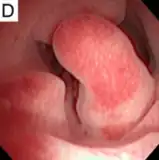

Hysteroscopy

Other tests include hysteroscopy.[2]

Pedunculated endometrial polyp

Pedunculated endometrial polyp Sessile endometrial polyp

Pathology

Endometrial polyps can be solitary or occur with others.[12] They are round or oval and measure between a few millimeters and several centimeters in diameter.[7][12] They are usually the same red/brown color of the surrounding endometrium although large ones can appear to be a darker red.[7] The polyps consist of dense, fibrous tissue (stroma), blood vessels and glandlike spaces lined with endometrial epithelium.[7] If they are pedunculated, they are attached by a thin stalk (pedicle). If they are sessile, they are connected by a flat base to the uterine wall.[12] Pedunculated polyps are more common than sessile ones.[11]